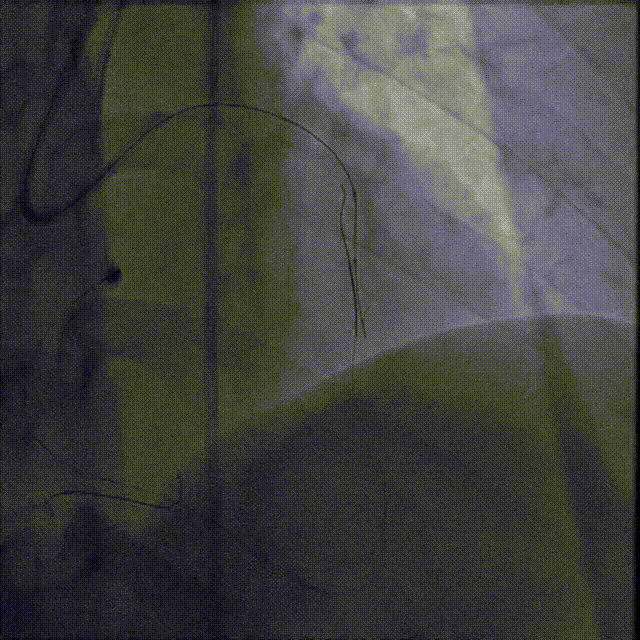

微导管高选择性造影(tip injection)显示远端心外膜侧枝迂曲

Caravel微导管支撑下,SUOH 03导丝通过心外膜侧枝送至LAD闭塞段远端

微导管“升级”通过侧枝

因侧枝血管严重迂曲,Caravel微导管无法通过侧枝,遂更换为1.5F HighTrack微导管顺利通过侧枝进入LAD远端

HighTrack微导管支撑逆向导丝前推至CTO病变体部,并跟进导丝进入CTO病变

应用Reverse CART技术成功通过闭塞病变

逆向导丝送至LAD近端,沿正向导丝送入2.0mm球囊扩张,在HighTrack微导管支撑下应用Gaia Third、Conquest pro 12导丝尝试Reverse CART成功